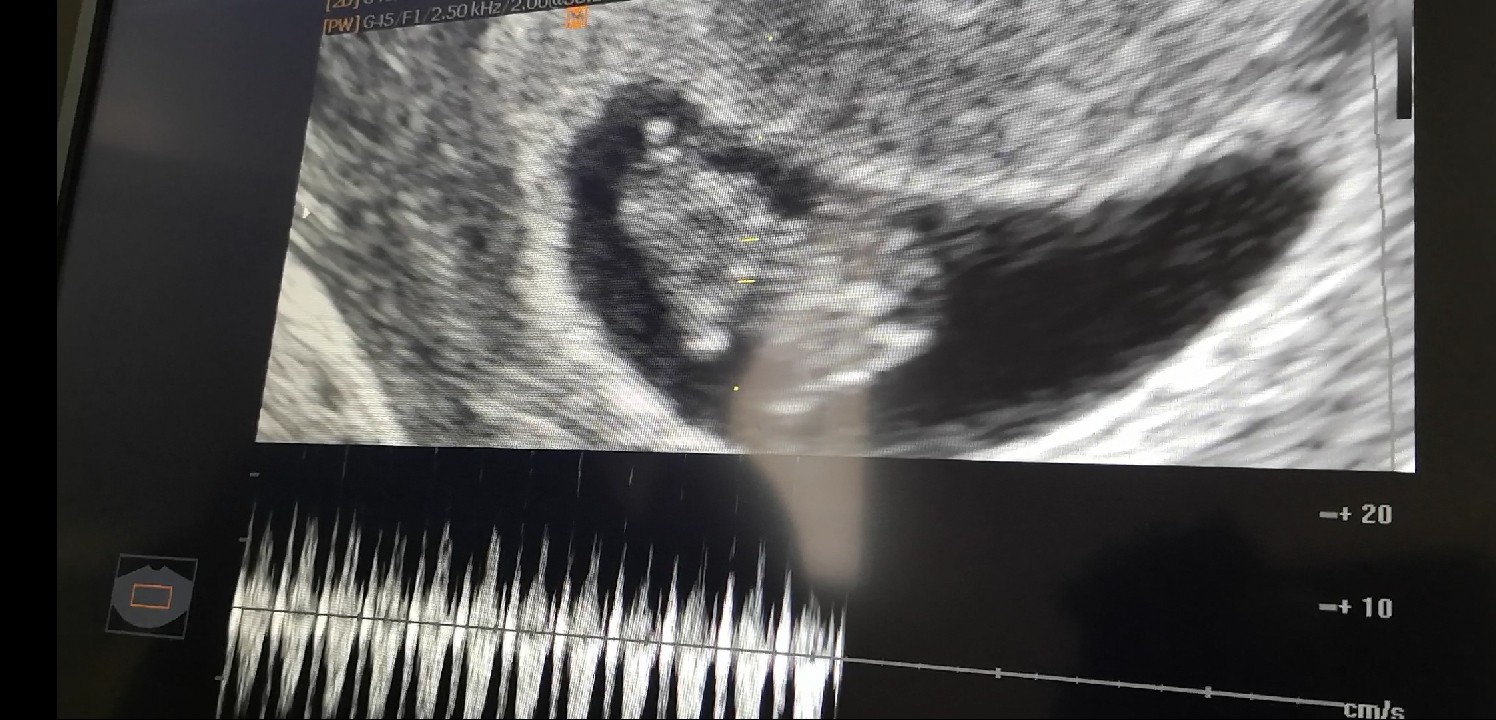

@Martusia1992 słodziak na tym zdjęciu

pamiętam jak mój bobas na USG tak machał rączkami i nozkami. Super widok

Ja już po wizycie, z Dzidzą na szczęście wszystko jest ok, nie wiadomo skąd to plamienie, teraz już jest czysto.

Byłam u lekarza, okazało się że miała małego krwiaka wielkości 0,68 cm który odpadł stąd plamienie. Dziecku nic nie jest dostałam Duphaston i mam mieć kontrolę za tydzień